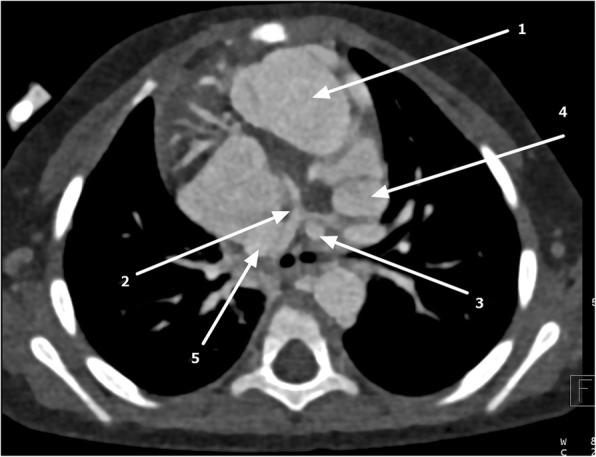

We report a case of a 31- month-old infant black girl in Tanzania who presented with an on-and-off history of difficulty in breathing, easy fatigability, facial and lower-limb swelling, recurrent respiratory tract infections, and failure to thrive.

我们报告了一名来自坦桑尼亚的31个月大黑人女婴的病例,该患儿有断断续续的呼吸困难、易疲劳、面部和下肢肿胀、反复呼吸道感染以及发育不良的病史。